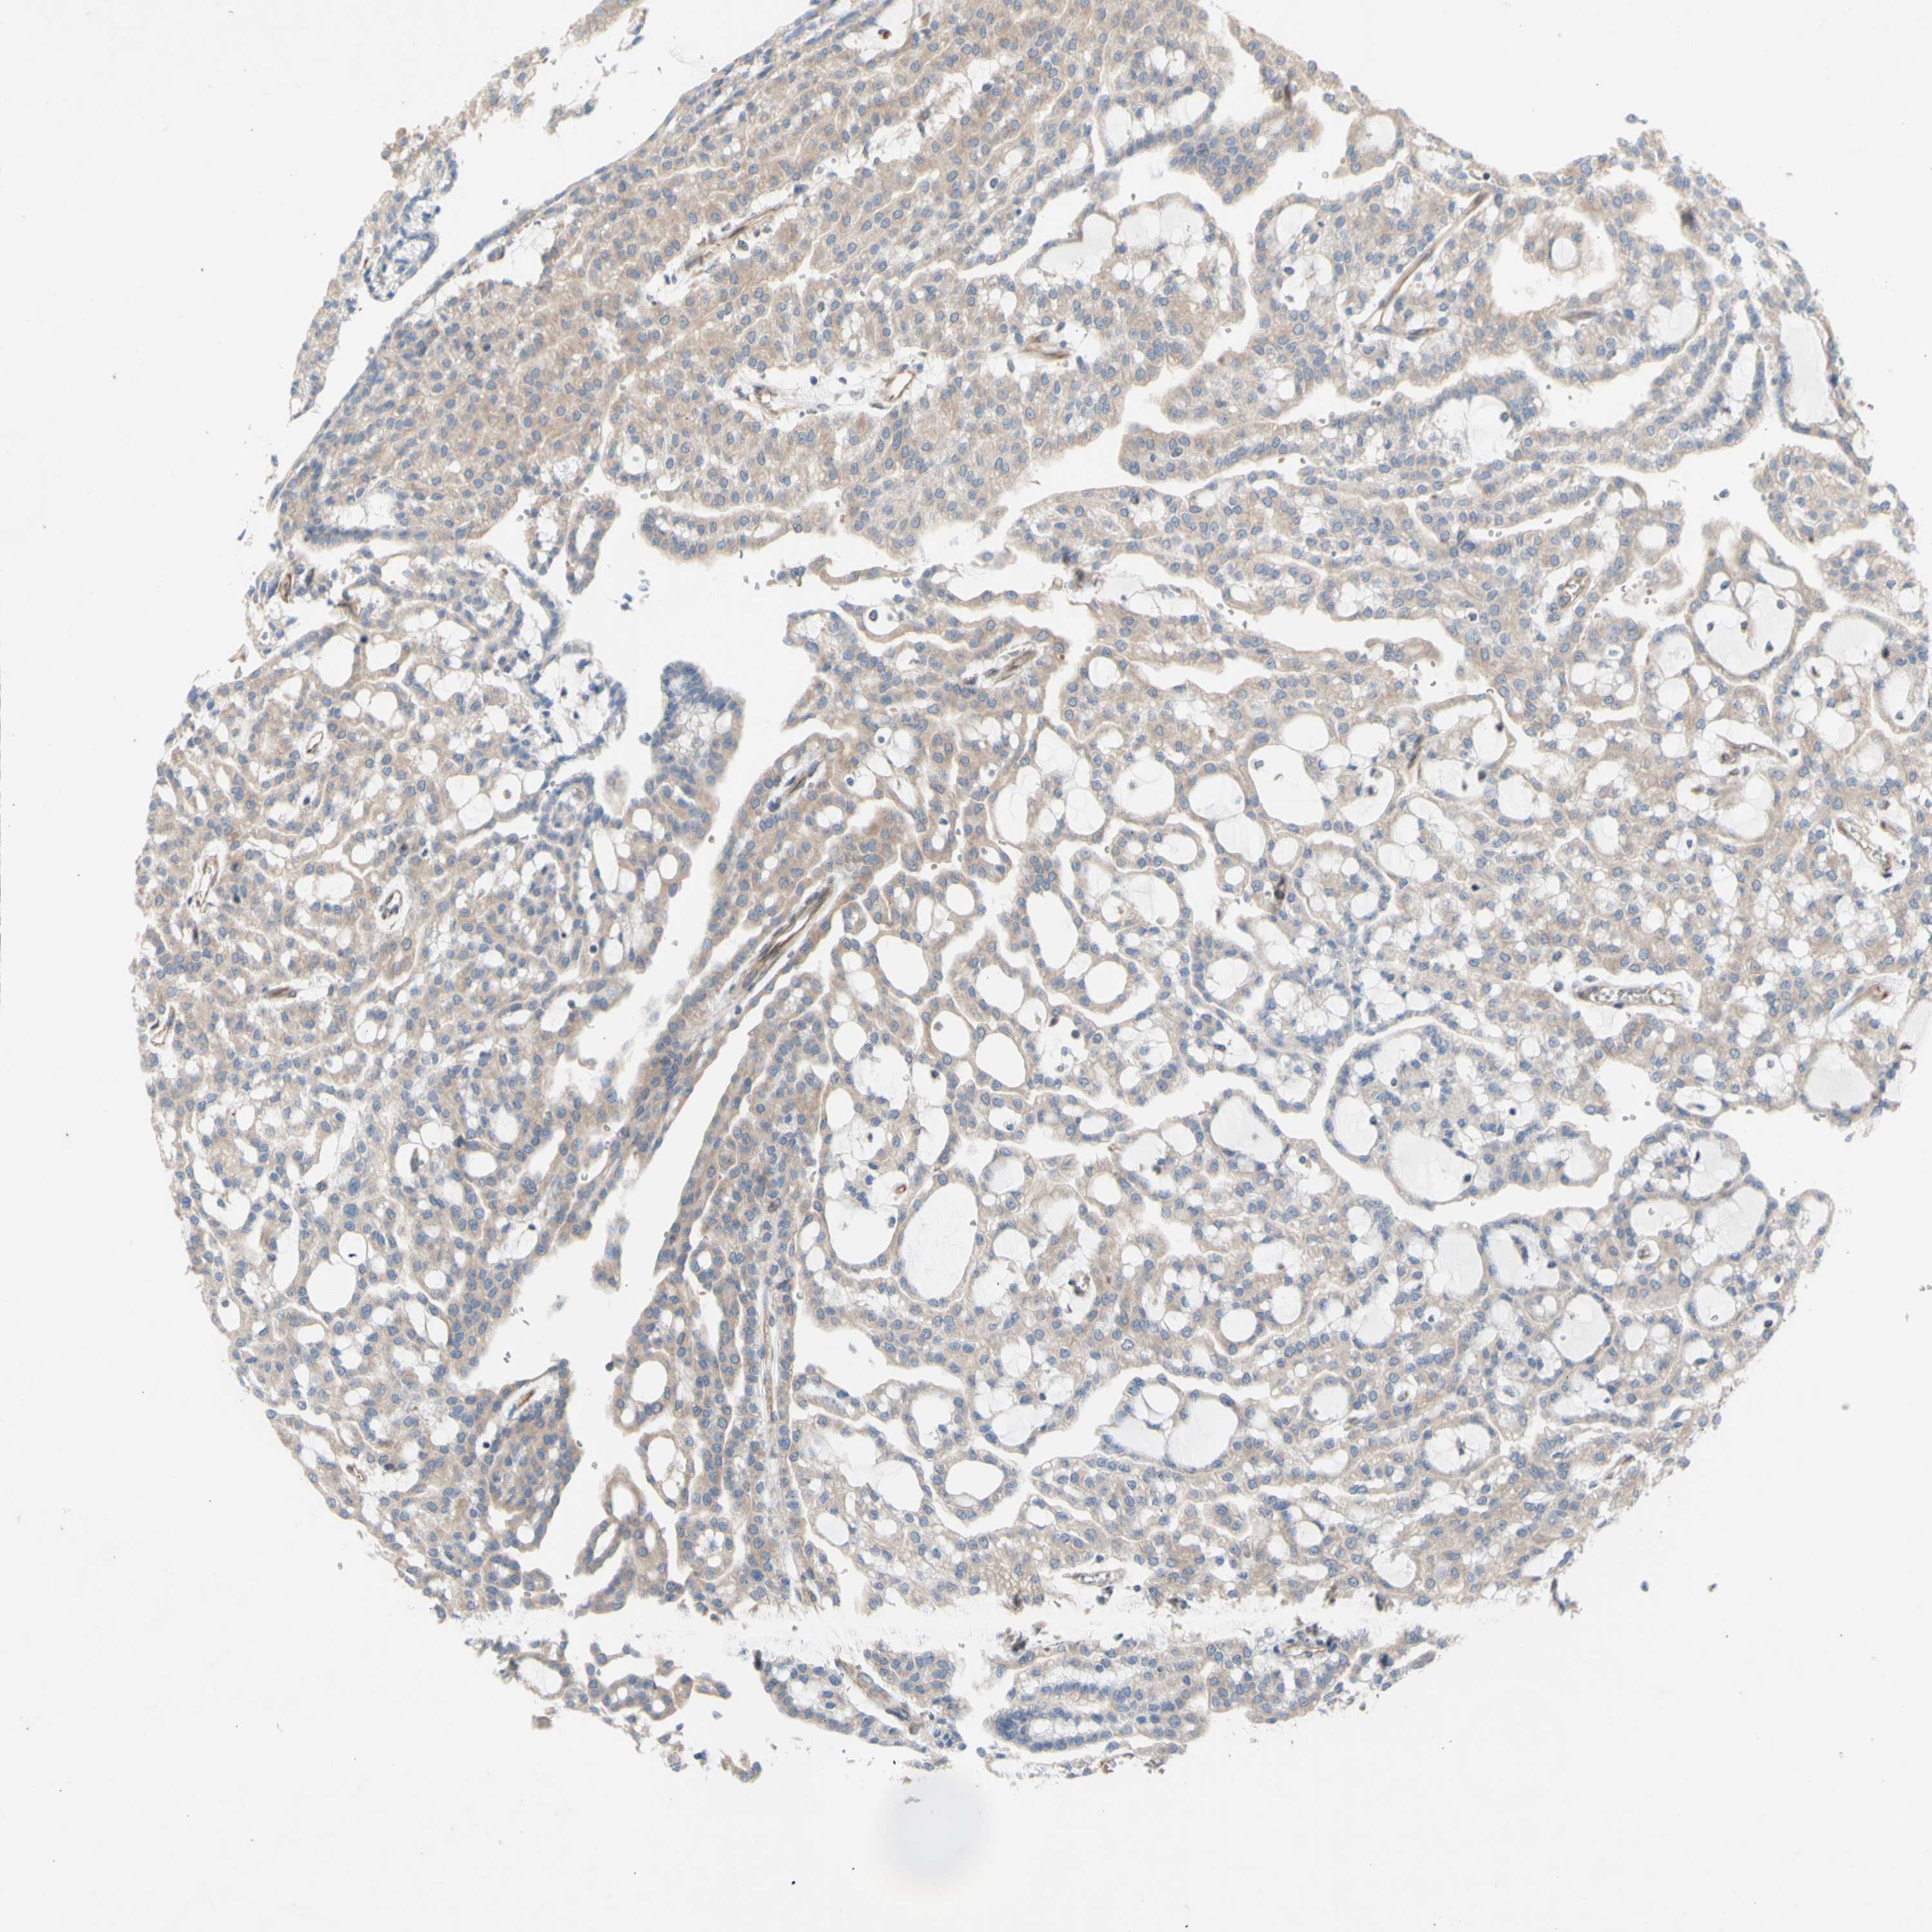

TCGA RNA samplesi

RNA-seq data is reported as average FPKM (number Fragments Per Kilobase of exon per Million reads), generated by the The Cancer Genome Atlas (TCGA) .

Normal distribution across the dataset is visualized with box plots, shown as median and 25th and 75th percentiles. Points are displayed as outliers if they are above or below 1.5 times the interquartile range. FPKM values of the individual samples are presented next to the box plot.

Average pTPM 43.9

Number of samples 100